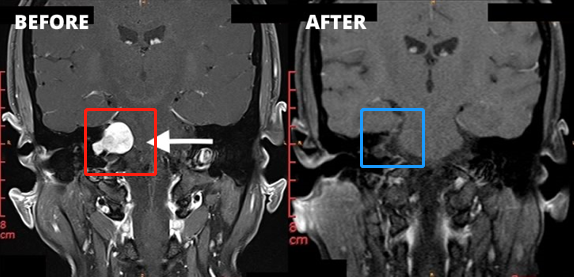

1、左侧图示(红色)患者术前核磁:右侧桥脑小脑角区见一类圆形占位性病变,边界清楚,T2WI高信号,其内信号欠均匀,增强扫描后病变呈明显强化,同侧桥脑小脑角池扩大,内听道扩大,四脑室轻微受压。

2、右侧图示(蓝色)患者术后核磁:术后肿瘤切除干净,做到了全切全切,核磁未见占位性病变。与术前对比明显可见肿瘤完整切除,较大限度减少复发可能。

3、患者术前情况:右耳耳鸣3个多月,听力下降,头昏头痛加重。面肌抽搐、舌头、牙龈和脸有麻木感觉,无法正常生活。

4、患者术后情况:术后1周出院,术后2周面神经功能House-Brackman分级1级。面神经保留,没有面瘫,听力保留。术后9个月随访,恢复很好,能够正常生活。

5、手术总结:听神经瘤切除手术规模较大的挑战是确定90%以上切除率的同时,既不损伤听神经、听力,也不损伤面神经,不会发生面瘫。以上肿瘤全切术由巴特朗菲教授操作,术后听力保留较好,且无面瘫。这样的手术效果堪称,这样的技术手法和水平即使是国际神经外科医院案例中也可以作为教科书级别的案例。